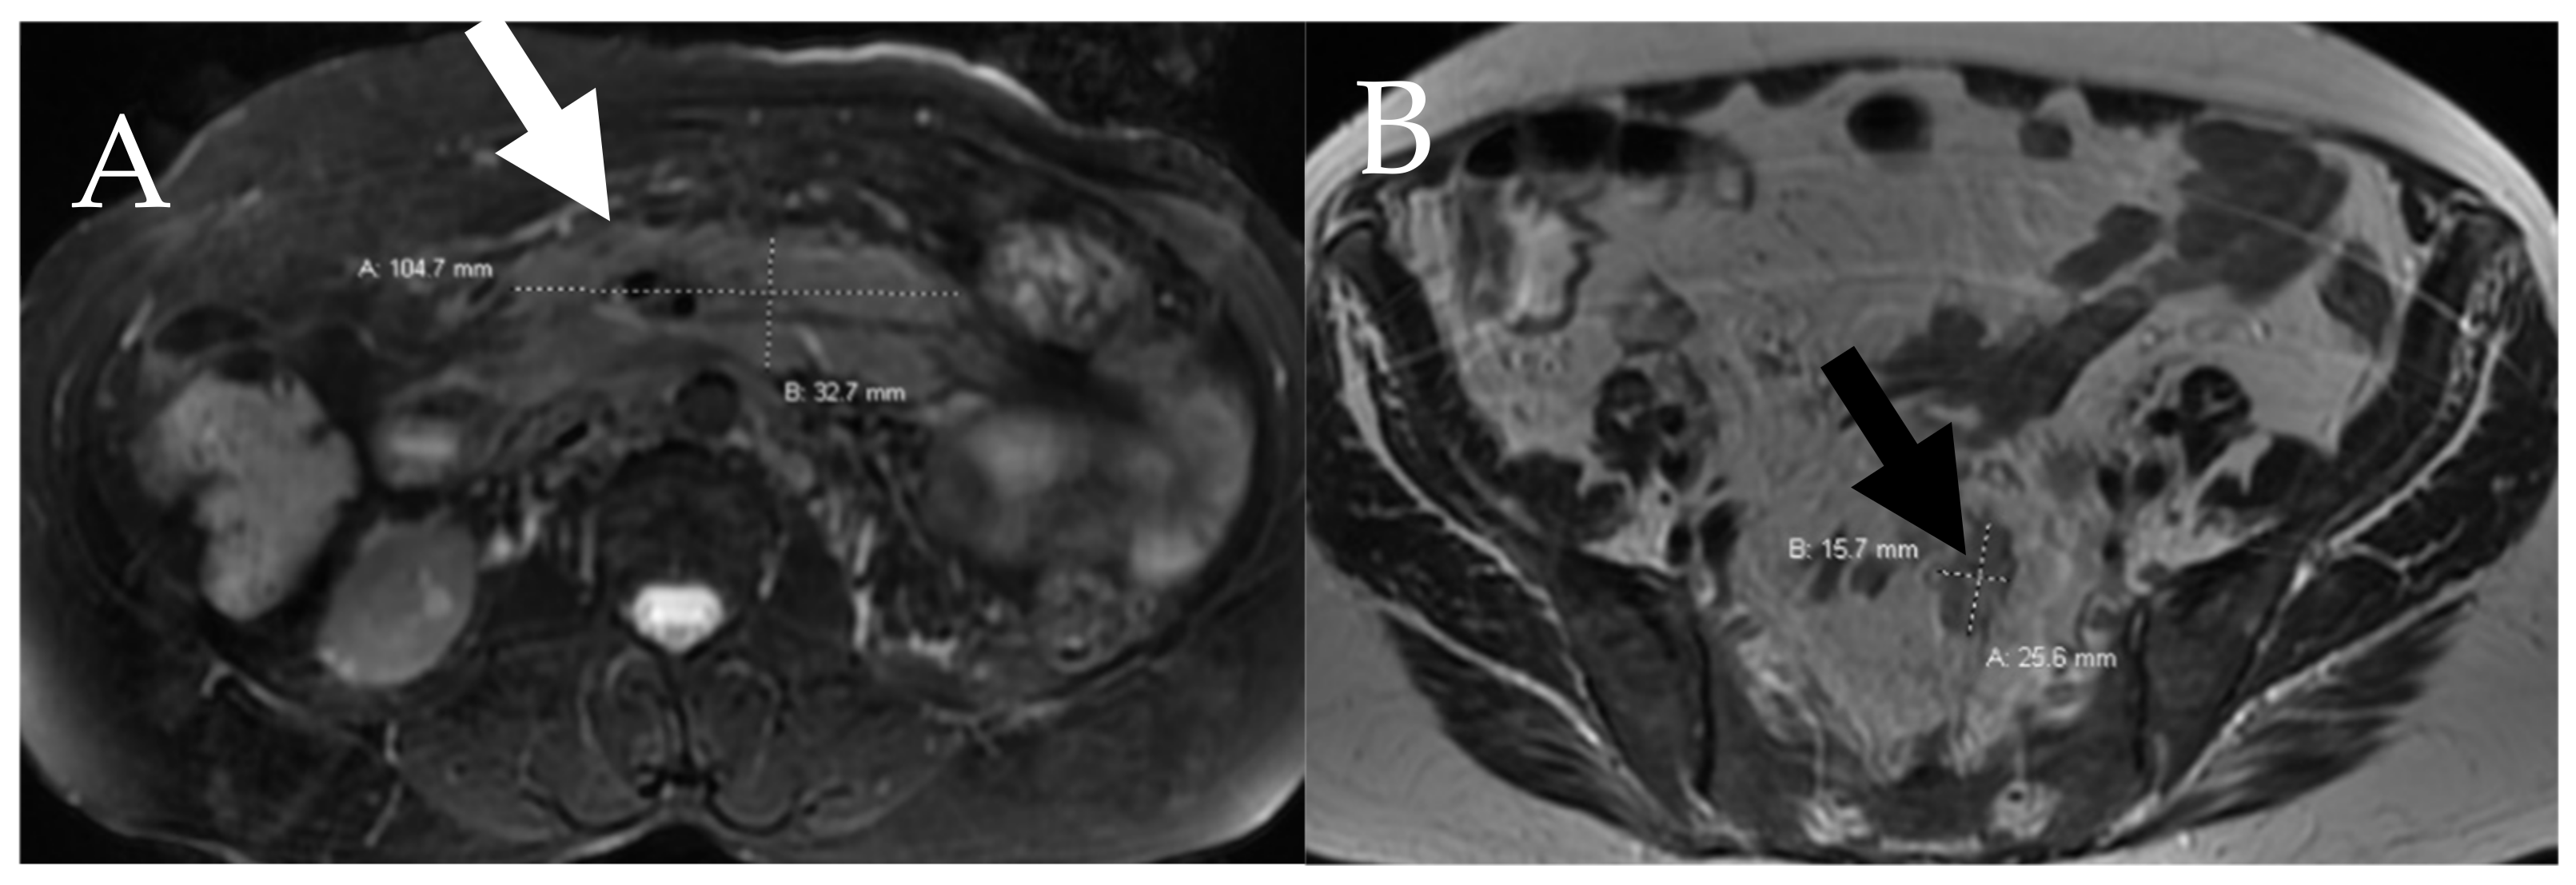

6.4. Lymphatic